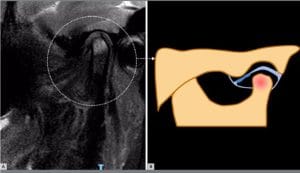

Este estudo avalia a associação entre deslocamento do disco articular da articulação temporomandibular (ATM) e osteoartrose, utilizando imagens de ressonância magnética para identificar alterações degenerativas. Os resultados apontam maior probabilidade de osteoartrose, especialmente em casos de deslocamento anterior do disco sem redução (ADDwoR).

Avaliar o odds ratio (OR) de articulações com deslocamento do disco apresentando osteoartrose, por meio da análise por ressonância magnética.

As articulações com ADDwR apresentaram 2,73 vezes mais chances de ter osteoartrose, enquanto as com ADDwoR apresentaram 8,25 vezes mais chances. A ocorrência de osteófitos foi 9 vezes mais provável nos casos de ADDwoR, em comparação com OR 2,96 para ADDwR.

A significativa razão de chances de articulações com deslocamento do disco apresentando osteoartrose, especialmente nos casos de ADDwoR, destaca a importância de uma avaliação precisa das alterações na posição do disco, que podem estar associadas a outras disfunções dolorosas e funcionais da ATM.